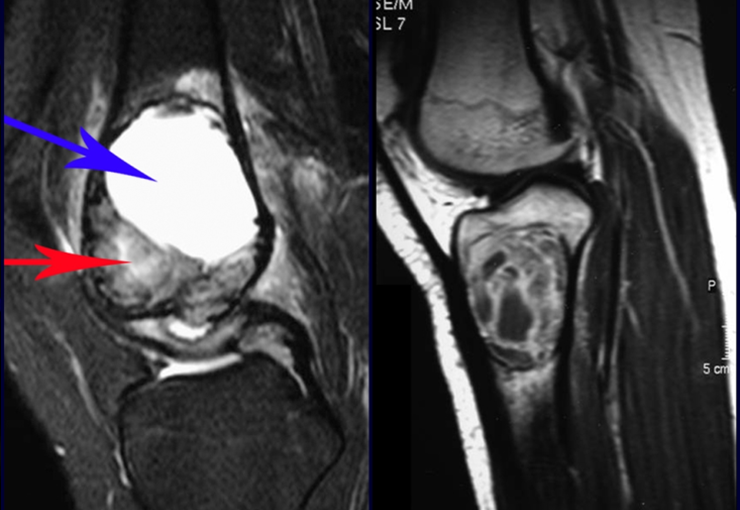

A escolha do local de biópsia deve permitir a obtenção de amostra representativa da heterogeneidade da lesão: A) COA ; B) TGC

Observa-se que a lesão apresenta áreas de conteúdo líquido (a-COA) e áreas sólidas (b-TGC).

Deve-se analisar cuidadosamente a anamnese e as imagens da lesão, escolher o sitio da biópsia que permita colher amostra das diferentes áreas que se apresentam heterogêneas na ressonância magnética, para permitir o diagnóstico preciso.

O cisto ósseo aneurismático clássico tem aspecto homogêneo, enquanto as lesões tumorais citadas, quando acompanhadas de áreas de cisto ósseo aneurismático, tornam-se obrigatoriamente heterogêneas.

A ressonância magnética por realizar cortes em diferentes planos mostra com freqüência a presença de níveis líquidos, evidenciando as numerosas bolsas separadas pelos septos conjuntivos. O diagnóstico de cisto ósseo aneurismático na biópsia é aceito com maior tranqüilidade quando na análise da ressonância de toda a lesão não se evidencia nenhum aspecto heterogêneo. A presença de estrutura heterogenia na ressonância magnética, em que a área sólida apresenta impregnação de contraste, implica na necessidade de se obter amostra desta área para o diagnóstico, pois deve tratar-se de caso de associação de cisto ósseo aneurismático com alguma das lesões citadas.